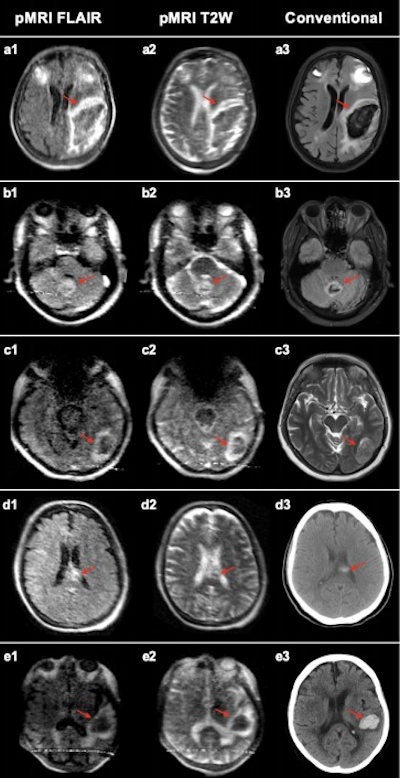

Mazurek's group compared results of 144 scans acquired with the system at bedside at Yale New Haven Hospital between July 2018 and November 2020 using the portable MRI scanner to results from traditional brain scans (noncontrast CT or 1.5-tesla/3-tesla MRI).

Two radiologists evaluated the 144 portable MRI scans taken. Of these, 56 were intracerebral hemorrhage, 48 were acute ischemic stroke, and 40 were healthy controls.